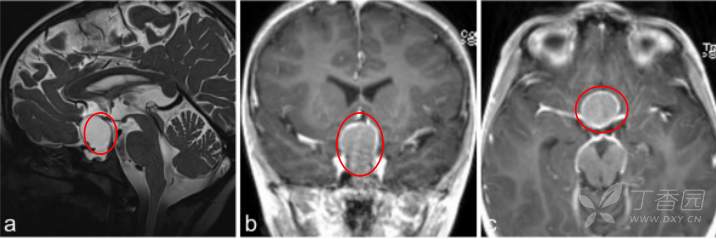

7岁男孩出现垂体功能减退的症状,如体重减轻、生长发育停滞、身体状况不佳和疲劳。就诊四周前,他一直抱怨头痛和呕吐,评估表明是全垂体功能减退。

a–c图MR成像显示囊性病变对比增强,高度怀疑颅咽管瘤